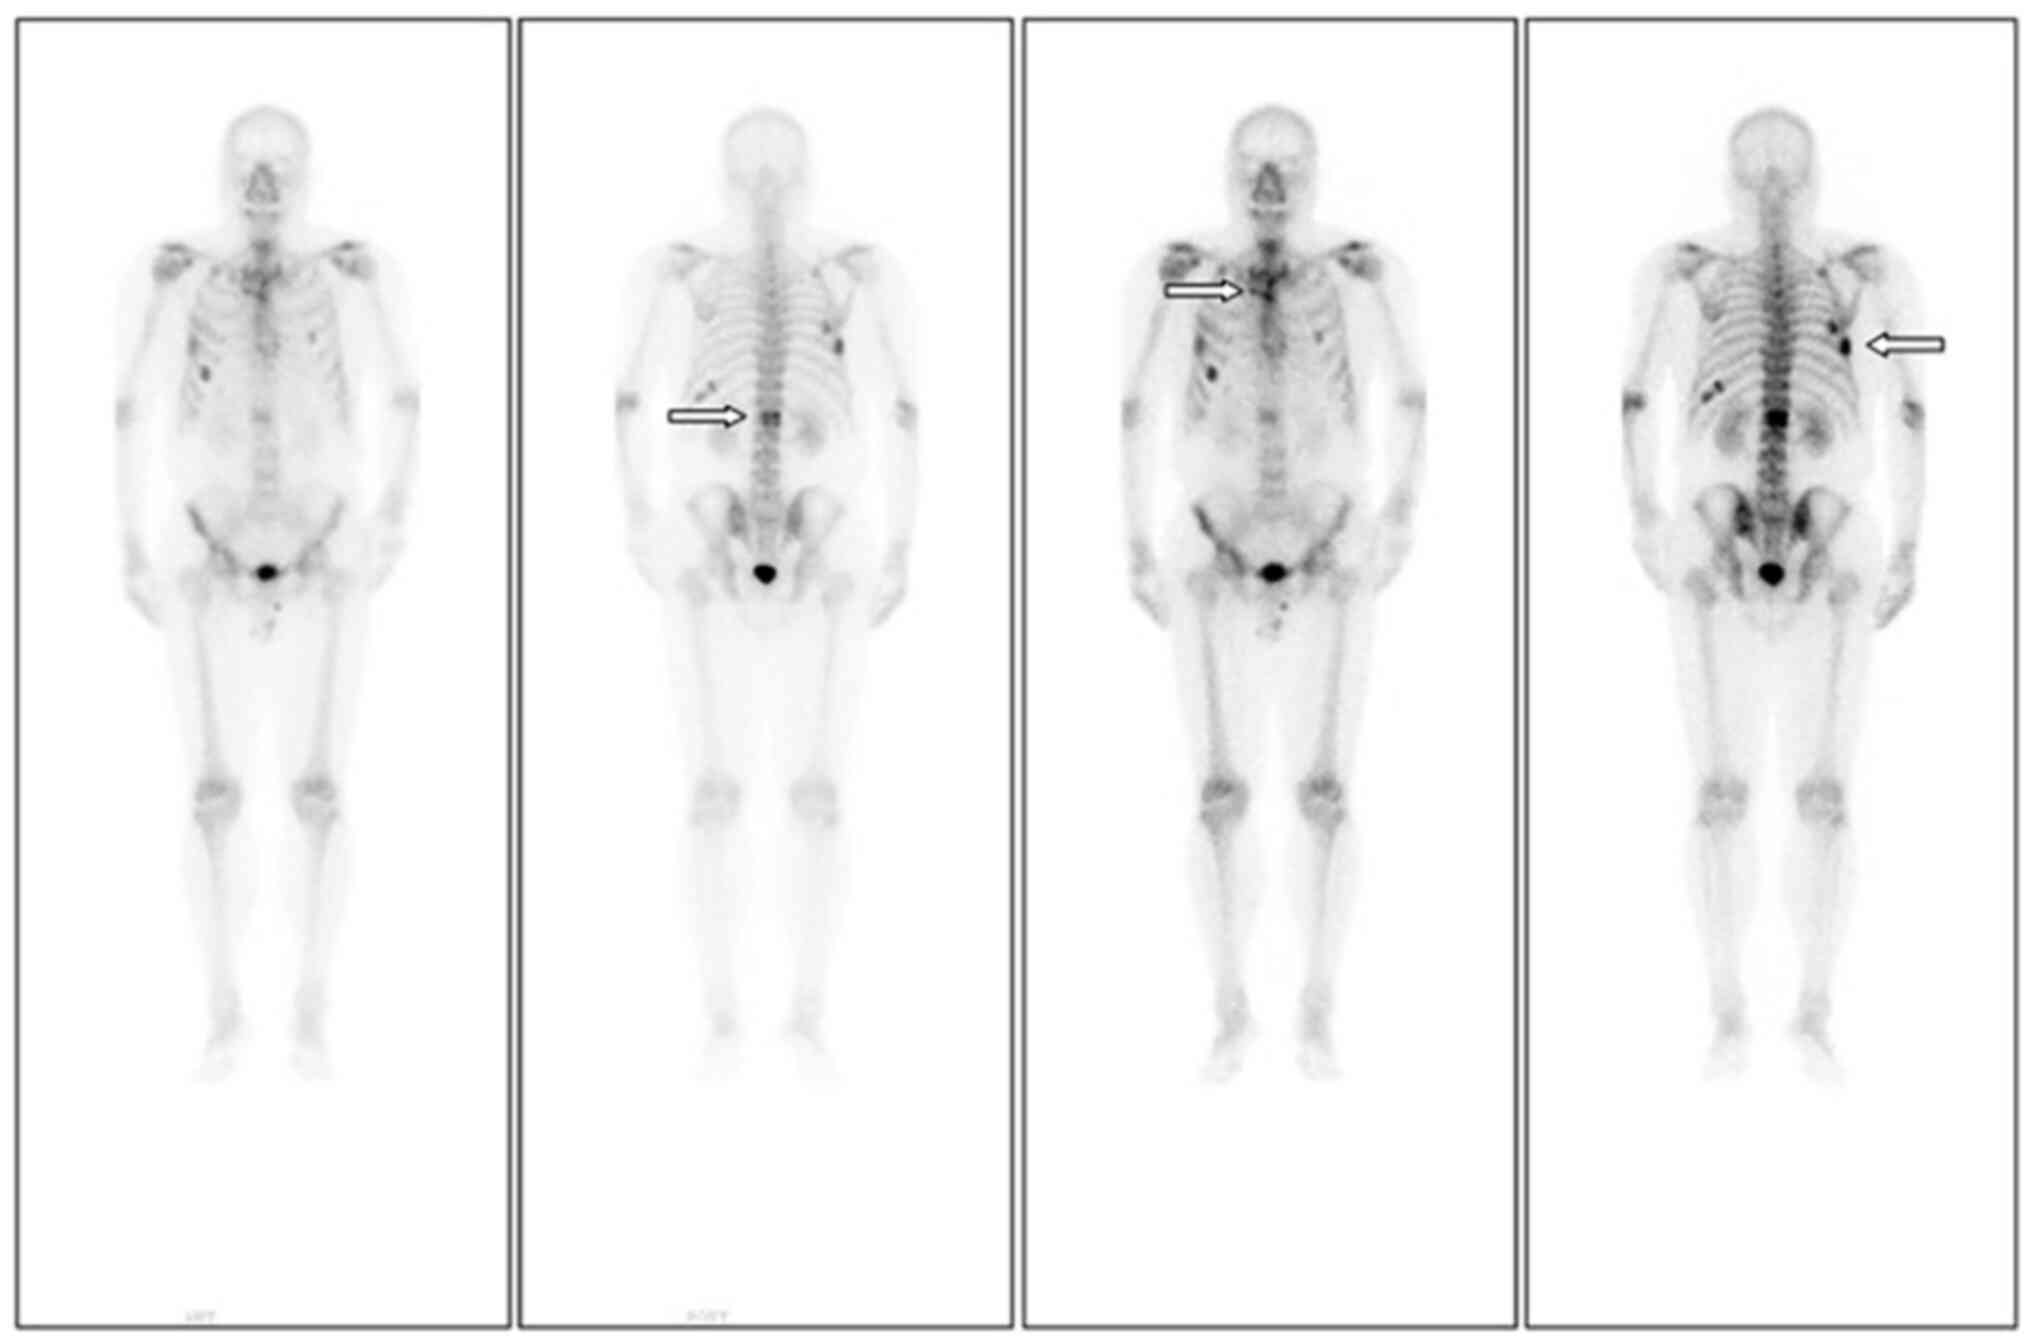

Figure 3.

One year after the onset of bone pain, ECT was performed, indicating active bone metabolism in the right seventh rib (fourth column arrow), upper sternum (third column arrow) and first lumbar spine (second column arrow). Compared with the previous ECT results, new lesions were identified. However, compared with the positron emission tomography/computed tomography results, no new lesions were found, though the local lesions had progressed. ECT, emission computed tomography.

Subsequently, the patient presented with a lump around the colostomy stoma site and intermittent abdominal pain in November 2020. Physical examination revealed a lump measuring ~10×10 cm around the stoma, which did not reduce in size when the patient was lying flat. Abdominal CT (Fig. 4) revealed that the intestinal tube had protruded into the subcutaneous fat layer of the abdomen. Based on the patient's medical history, physical examination (a lump around the colostomy stoma site) and the result of abdominal CT (Fig. 4), a parastomal hernia was suspected. Surgery was the recommended treatment. Routine preoperative blood tests, coagulation function, and liver and kidney functions showed no abnormalities. Parastomal hernia repair surgery was performed using the keyhole technique in November 2020. A relatively soft drainage tube was placed subcutaneously in the surgical area. The patient recovered well after the surgery and was discharged on the third postoperative day without removing the drainage tube. During discharge, the surgical area was not compressed. However, five days after discharge, the patient experienced swelling, pain and bleeding at the surgical site. Abdominal CT showed a hematoma in the surgical area (Fig. 5). After taking hemostatic treatment measures (hemostatic drugs, compression hemostasis), fresh blood still slowly flowed out from the drainage tube. Dynamic reexamination of coagulation function showed that it gradually deteriorated, and the activated partial thromboplastin time was gradually delayed to 60 sec, which was 20 sec longer than normal (reference range, 20–40 sec). The patient had stubborn anemia, and after multiple blood transfusions, no significant increase was identified in hemoglobin, which remained between 45–68 g/l (normal range, 130–175 g/l). A bone marrow biopsy was also performed to investigate the cause of persistent bleeding (Fig. 6). The bone marrow smear was stained using the Wright staining method and 200 cells were counted under a microscope. The results showed abnormal proliferation of plasma cell lines in bone marrow smears, accounting for 35% of total cells, with an immature plasma cell composition accounting for 21.0% of total cells (normal range, 0–0.8%). This result is consistent with the diagnosis of multiple myeloma (10,11). Fig. 6 shows the characteristics of abnormal plasma cells: This type of cell was significantly different in size, with the cell body and nucleus appearing circular, elliptical, ovoid or irregular in shape. The nucleus was misaligned, the chromatin of the nucleus appeared as a granular or loose network and certain cells showed obvious nucleoli. The cytoplasm was rich, stained opaque dark blue and flame-like, with obvious light staining bands around the nucleus. Nodular protrusions and vacuoles were easily observed, while no particles were seen. The morphological features were consistent with those of MM (10). Further testing revealed elevated serum immunoglobulin A (IgA) levels of 76.7 g/l (normal range, 0.82–4.53 g/l) and significantly increased serum β2 microglobulin (β2-microglobulin) levels of 16,205 ng/ml (normal range, 604–2,286 ng/ml). Based on the results of the bone marrow puncture, the bone destruction, anemia and bleeding were attributed to MM. After consultation with a hematologist, the patient was diagnosed with MM (IgA-λ type, Durie-Salmon Stage III). The Durie-Salmon staging system is a classic staging system for MM. The staging criteria for Stage III are as follows: One or more of the following abnormalities must be present: Hemoglobin <8.5 g/dl; serum calcium >12 mg/dl; very high myeloma protein production; IgG peak >7 g/dl; IgA peak >5 g/dl; Bence Jones protein >12 g/24 h; and >3 lytic lesions on bone survey (11). The patient was transferred to the hematology department and was treated with the PCD regimen (bortezomib, cyclophosphamide, dexamethasone), chemotherapy and blood transfusion. The specific dosage of medication is calculated based on the patient's body surface area. One chemotherapy cycle is 4 weeks and this patient received 6 cycles of chemotherapy. Afterwards, the patient received maintenance treatment with bortezomib monotherapy. The seventh rib lesion invaded the surrounding soft tissue, and the interventional department performed an empty needle puncture biopsy on it. The pathological and immunohistochemical results of the puncture tissue are consistent with multiple myeloma (10). The lesion was determined to be plasmacytoma, suggesting involvement of MM (Fig. 7), and the immunohistochemical results were as follows: CD138 (+), CD38 (+), cytokeratin (CK) (−), Ki67 (15%, +), Lambda (+) and MM oncogene 1 (+) (Fig. 8). CK negativity indicated the absence of malignant cells of epithelial origin. The patient's condition gradually improved, with increasing hemoglobin levels, recovering coagulation function, absorption of the hematoma around the stoma (Fig. 9) and alleviation of bone pain. For the past 2 years, the patient has been regularly treated in the hematology department and the progression of the MM has been slow (Figs. 10 and 11). Fig. 10 is a PET/CT image of the patient diagnosed with MM one year later. The arrows in Fig. 10 indicate the metabolic status of the lesionsin the right seventh posterior rib, upper sternum, and first lumbar spine. The increased metabolism of these three main lesions is consistent with the manifestation of MM. In Fig. 11, row A represents the situation of lesion in the upper sternum at different time-points; row B shows the situation of lesion in the upper sternum at different time-points; and row C shows the situation of lesion in the upper sternum at different time-points. The arrows in Fig. 11Aa, Ba and Ca refer to the lesions of the upper sternum, the seventh rib on the right side and the first lumbar vertebra when MM was diagnosed. Fig. 11Ab-Cb shows the respective lesions 1 year after the diagnosis of MM and Fig. 11Ac-Cc shows them at 2 years after the diagnosis of MM. After comparison, the progression of these three lesions was not obvious. After treatment, the soft tissue mass around the lesion of the right seventh rib gradually became smaller. The patient has not experienced any worsening bone pain symptoms since being diagnosed with MM. The patient has been regularly visiting the hematology outpatient department. During the follow-up period, the patient's blood routine, coagulation function and serum immunoglobulin are being tested every two months, and chest CT and spinal CT examinations conducted every 6 months. During follow-up, there has been occasional mild anemia but no coagulation abnormalities.

Figure 10.

Positron emission tomography/computed tomography examination after 1 year of diagnosis of multiple myeloma. The upper sternum, right seventh rib and first lumbar spine still have obvious lesions (arrows).

Figure 11.

Images of lesions at different stages after diagnosis of MM. (Aa-Ca) Lesion images at the time of diagnosis of MM. The arrows refer to the lesions of (Aa) the upper sternum, (Ba) the seventh rib on the right side and (Ca) the first lumbar vertebra when MM was diagnosed. (Ab-Cb) Local lesions diagnosed as MM after 1 year of treatment. (Ac-Cc) Local lesions diagnosed as MM after 2 years of treatment. MM, multiple myeloma.